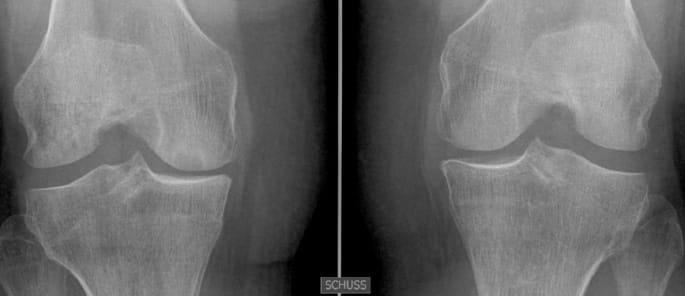

Traumatologie - Orthopédie Mise au point : les plasties extra-articulaires du genou associées aux ligamentoplasties du LCA